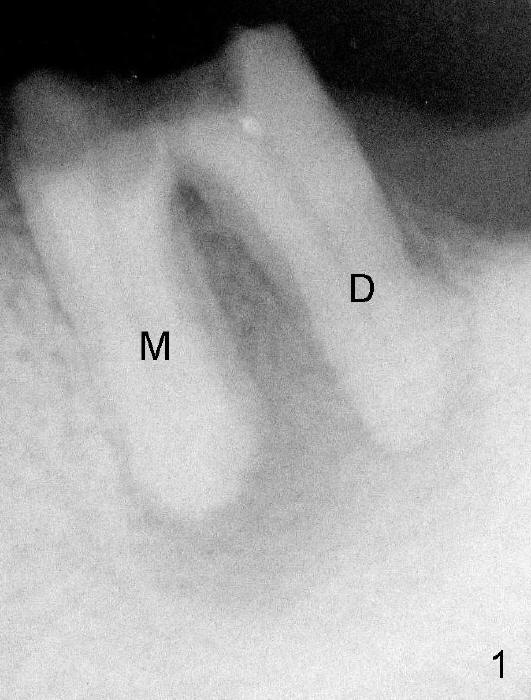

Preop PA shows extensive bone loss around the residual roots (Fig.1). M: mesial; D: distal.